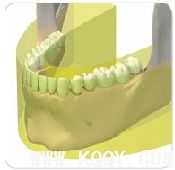

前牙掃描層增厚技術(shù)與傳統(tǒng)的前牙掃描攝影技術(shù)相比,提高了病人前牙區(qū)圖像質(zhì)量

其他口腔全景機(jī)前牙掃描層厚較窄,導(dǎo)致病人定位困難。

CRANEX D將前牙掃描層厚增加50%,提高前牙區(qū)圖像質(zhì)量,并使病人定位簡便。